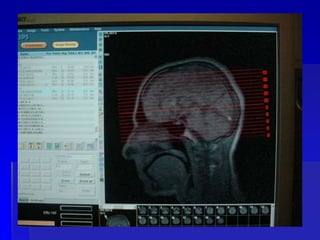

COMO CONSIGO PROGRAMAR

CADA CORTE?

PLANEJAMENTO